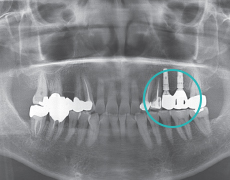

Schritt 2

Primäroperation (Einsetzung künstlicher Wurzeln)Das Implantat wird in die jeweilige Stelle eingesetzt.

Sekundäroperation (Osseointegration und Pfeilerverbindung)Das Implantat wird freigestellt, um es an den Pfeiler zu verbinden.